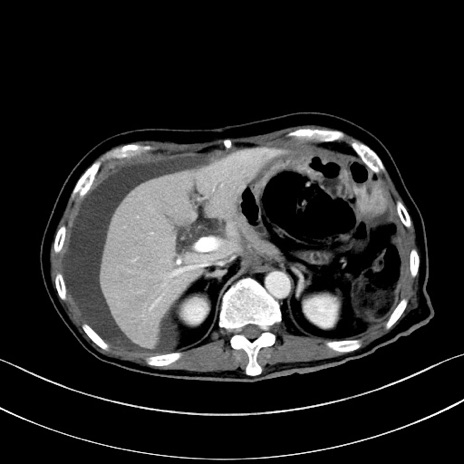

冠状断像

【症例】60歳代男性

【主訴】嘔吐

【現病歴】胃癌にて胃全摘後。食思不振が悪化し、夜中に嘔吐することがある。

【既往歴】胃癌、胃全摘、脾摘、胆摘後

【データ】WBC 5900、CRP 10.56